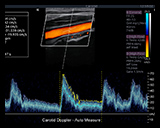

Color Doppler

- Adaptive Doppler Imaging Automatically and continuously adapts to the flow state to optimize color fill-in, boundary detection and hemodynamic display.

- Supported modes: Velocity, Power Doppler Imaging (PDI), Directional PDI (DPDI)

- Side-by-side live format B-mode/color Doppler

- Additional optimization parameters: Gain, dynamic range, frame rate, frequency | Persistence, smoothing, wall filter, map | Steer angle, scale, invert, baseline, threshold

Strip Doppler

- Supported modes: PW, CW

- HPRF: Automatic invocation as needed to maintain gate location/scale

- Auto Doppler measurements: User selectable sensitivity and direction

- Duplex and Triplex displays

- Additional optimization parameters: Scale, Gain, Dynamic range, Wall Filter, Sweep speed, Baseline, Angle, Steer, Invert, Volume, Map and Tint, Frequency, Gate size, Strip size: Selectable top-bottom split screen display including full strip